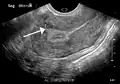

الفحص باليدين قادر على تحديد وجود الأورام كبيرة الحجم، يعد استخدام الموجات فوق الصوتية أداة التشخيص المثالية لتقدير وجود الورم. يصف التخطيط بالموجات الصوتية الورم على أنه كتل بؤرية غير متجانسة النسيج، والتي تؤدي إلى تظليل في الإشعاعات فوق الصوتية، ويمكن تحديد موقع وأبعاد الورم، كما يمكن استعمال التصوير بالرنين المغناطيسي لوصف الورم وأبعاده وموقعه في الرحم. طرق التصوير لا يمكنها التمييز بدقة بين الورم الخبيث والحميد، على الرغم من أن الورم الخبيث يعد نادرا. النمو السريع أو المفاجئ بعد انقطاع الطمث سوف يزيد الشك من وجود ورم خبيث في الرحم، وقد يكون هناك آثار غزو للأنسجة المحيطة. نادرا ما يتم أخذ خزعة للتشخيص، وإذا تم أخذها، فإنها لا تكون تشخيصية، واذا لم يكن هنالك تشخيص واضح بعد التصوير، يتم الإيعاز بالجراحة . ومن طرق التصوير الأخرى التي لها أهمية في تقييم الورم الذي يؤثر على التجويف الرحمي: تصوير الرحم وقنوات فالوب، والتصوير بالموجات الصوتية بعد ملئ الرحم بسائل .

ورم ليفي عضلي كبير تحت الطبقة المخاطية يملأ معظم التجويف الرحمي.